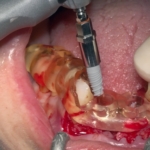

Rehabilitación completa maxilar (Full Arch)

Paciente: mujer, 59 años, edentulismo parcial.

Tratamiento: colocación de 6 implantes inmediatos con férulas apilables y prótesis provisional instantánea parcial.

Tiempo de intervención: 2 horas y 30 minutos.

Beneficios: intervención rápida y precisa, manejo conservador del tejido blando, estética y funcionalidad instantánea, alta satisfacción del paciente.

Estos casos ilustran cómo nuestro flujo BRDP y la cocreación clínica permiten resultados predecibles y eficientes, optimizando tanto el tiempo de sillón como la experiencia de paciente y clínica.